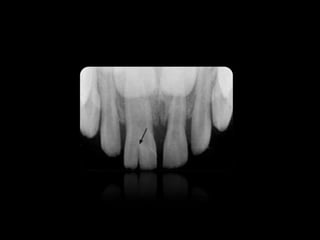

REABSORCIONES ÓSEAS